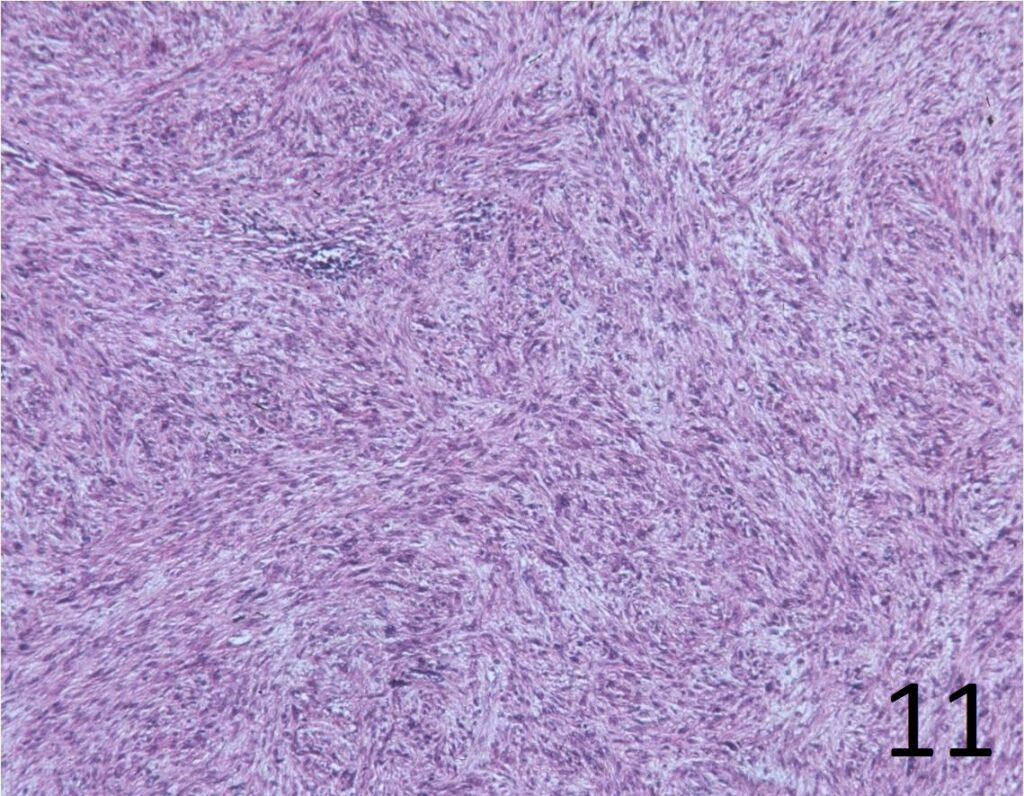

Microscopic

• Elongated, fairly uniform spindle cells with scant cytoplasm in a fibrous stroma

• Large nuclei with abnormal mitoses present; Higher grade tumors have more mitoses, necrosis and pleomorphism.

• Minimal pleomorphism with low grade tumors; More pleomorphism and mitoses with higher grade tumors

• Herringbone pattern (fascicles that intersect at right angles) (Fig. 11)